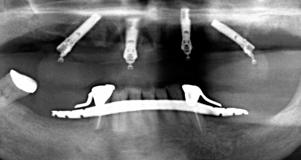

最低4本のインプラントを埋入し、それらを連結し、半日で固定式の仮歯まで入れて審美性、機能性を一日でとりもどせる革新的な治療。

3.インプラントの本数を少なくできることは、経済的も優れています。従来の治療では、無歯はでは10〜14本のインプラントを埋入していたのでそれと比較すると、かなりの治療費を削減できると考えます。